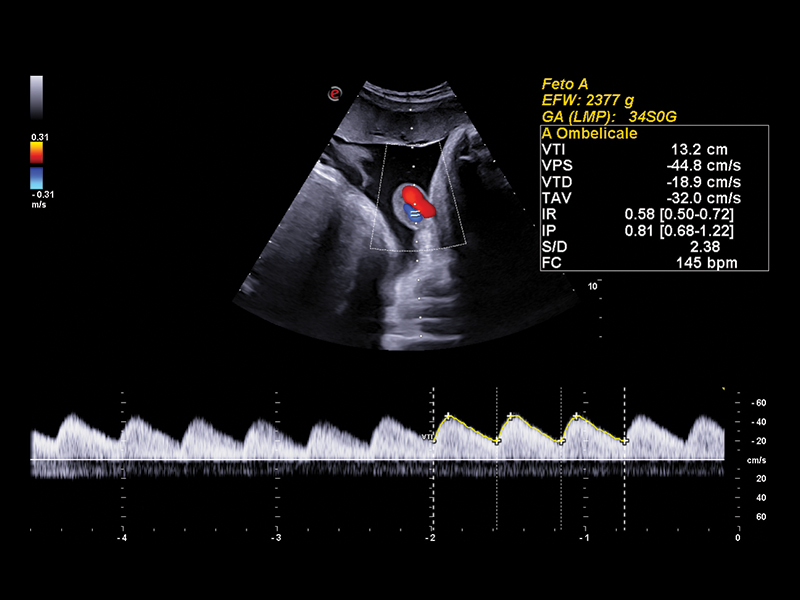

The clinical applications and uses of ultrasound in obstetrics are very broad and include gestational age assessment, artificial insemination, detection of multiple births, placenta localization, assessment of fetal wellbeing, and detection of fetal abnormalities.

Ultrasound also plays a major role in monitoring and management of high-risk pregnancies, thus reducing obstetric interventions and, above all, the risk of perinatal deaths.

Advanced Vascularization Imaging in Obstetrics Ultrasound

Bright Flow is the new convenient color map for blood flow through a blood vessel.If traditional flow images display flows in thin and flat sections, Bright Flow, with its 3D-like appearance, lead to an easier and faster hemodynamic visualization, including the tiniest internal structures of the heart. Achieve a new level of precision with microV HighFR (High Frame Rate) and XFlow, Esaote’s latest alternatives to Color Doppler, and don’t miss the option of exploring fetal brain microvascularization.

Clinical Images